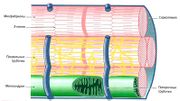

| 03:24, 20 июля 2016 | Mishci sport75.jpg (файл) |  |

53 КБ | Anes | Микроскопическое строение кардиомиоцита | 1 |